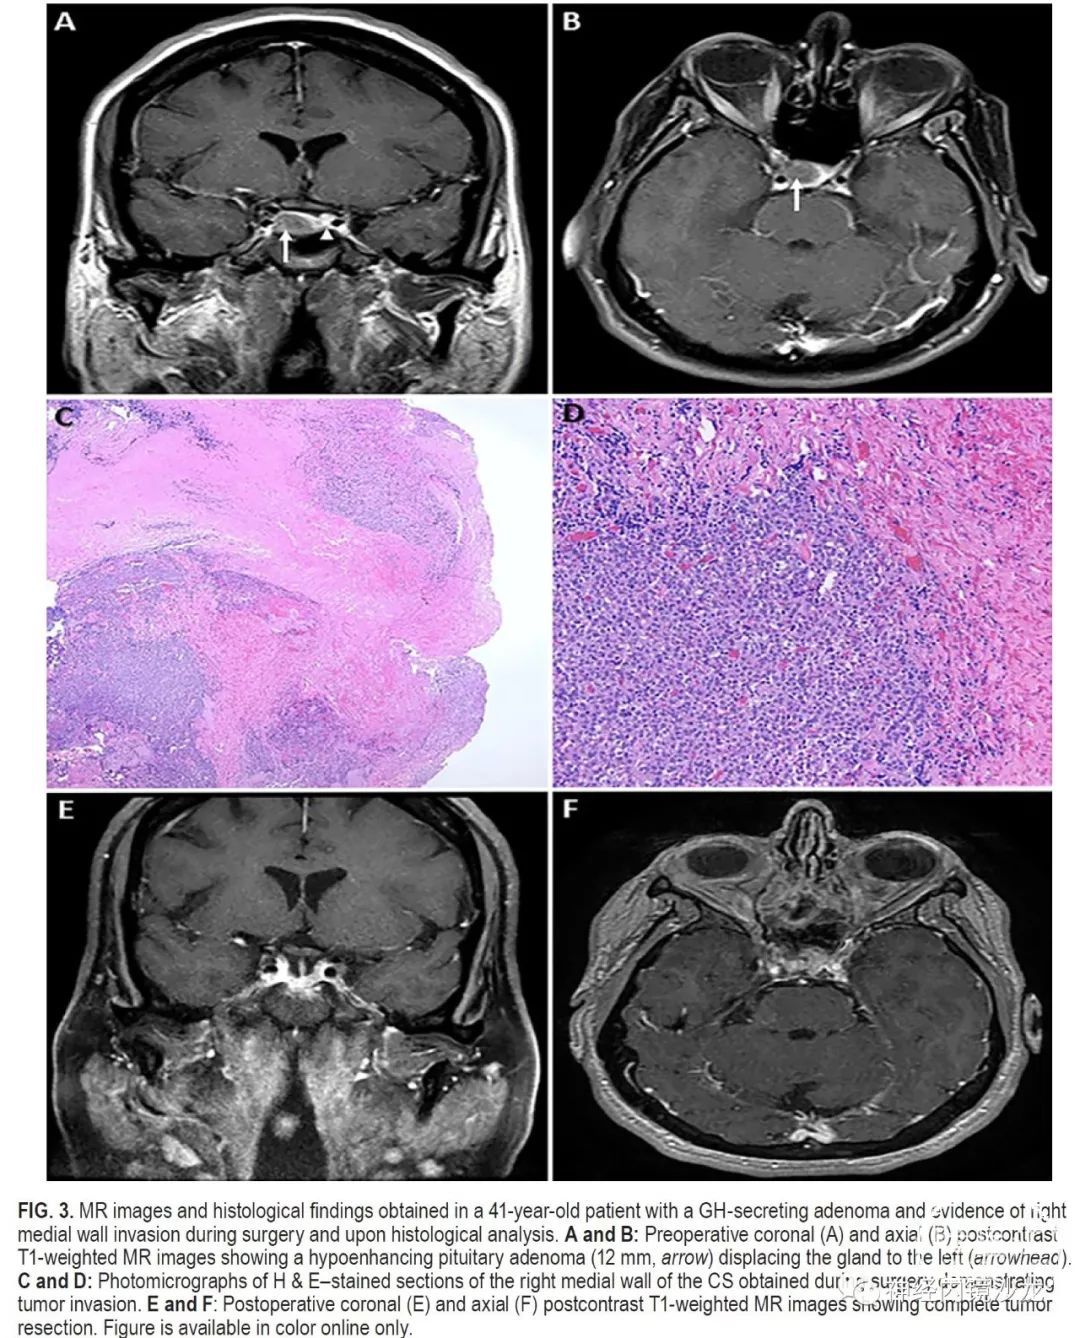

目的:垂体腺瘤常侵袭海绵窦(CS)的内侧壁,但由于存在血管和颅神经损伤的风险,通常不能外科手术切除。本研究的目的是报告一组大宗采用基于解剖学基础、分步选择性地手术切除海绵窦内侧壁的侵袭性垂体腺瘤病例的手术结果。

方法:对作者所在机构数据库进行了研究分析,筛选术中发现单纯侵犯内侧壁且采用内镜经鼻入路选择性切除海绵窦内侧壁的垂体腺瘤病例。排除侵袭海绵窦超出内侧壁的病例。对患者的并发症、切除率和缓解率进行评估。

结果:50例患者符合本研究的条件,15例(30%)非功能性腺瘤和35例(70%)功能性腺瘤;包括16例生长激素、10例催乳素和9例促肾上腺皮质激素(ACTH)腺瘤。非功能性腺瘤的平均肿瘤大小为2.3cm,功能性腺瘤的平均肿瘤大小为1.3cm。放射学检查,11例(22%)为Knosp 1级,23例(46%)Knosp 2级,16例(32%)Knosp 3级。根据术中判断和术后MRI,所有病例均实现肿瘤全切。对于功能性腺瘤患者,平均随访时间为30个月(范围4-64个月),对于非功能性腺瘤患者,平均随访时间为16个月(范围4-30个月)。根据最后一次随访结果,34例(97%)功能性腺瘤未采用辅助治疗即获得完全生化缓解(使用现行标准)。非功能性腺瘤的患者,未见影像学复发。50名患者中共切除了57侧内侧壁。组织学证实,93%的非功能性腺瘤和83%的功能性腺瘤中存在内侧壁侵袭。没有死亡或颈内动脉损伤病例,平均失血量为378ml。4名患者(8%)出现新发短暂性颅神经麻痹,其中2名患者需要再次手术清除血凝块和脂肪填塞物。未出现永久性颅神经麻痹。

结论:海绵窦内侧壁可以安全有效地切除,并发症低,完全切除和症状缓解率极佳。这种基于解剖学的手术技术的长期疗效,需要更多随访数据进一步确定。该技术只能由非常有经验的鼻内镜颅底团队进行。